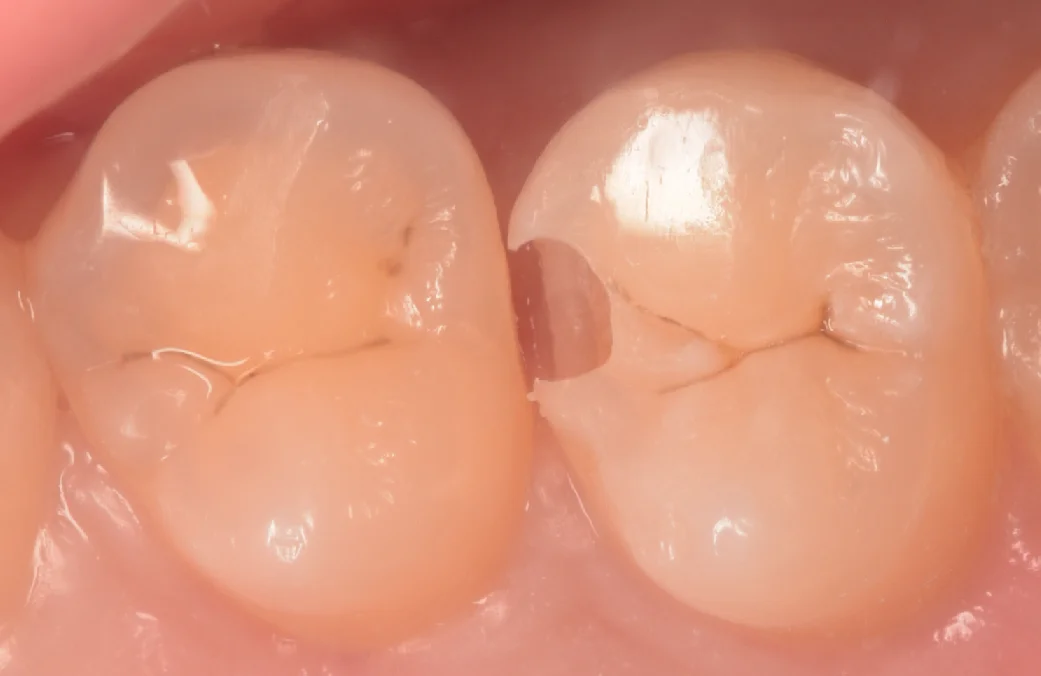

まずは術前からです。

画像中央の歯の間、右側の方に虫歯がありました。

見た目だと全くわからないですよね。

若い方の虫歯の場合、色が白っぽく、全く肉眼ではわからないことがあります。

こういうのをしっかりと見つけるためにはやはりレントゲンとの併用検査が必須だと思います。